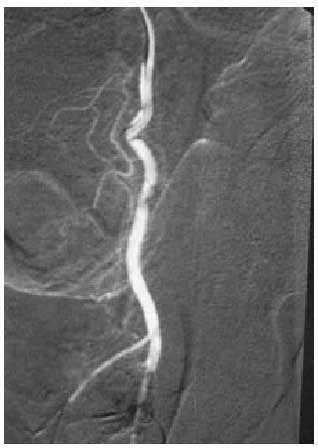

Al no existir un proceso isquémico, no suele dar lugar a complicaciones, por lo que el tratamiento no tiene tanta premura como en el de origen venooclusivo y, en consecuencia, se puede diferir (tal es así que incluso se ha planteado la no necesidad de tratar a estos pacientes). El objetivo terapéutico consistirá en disminuir el flujo de entrada mediante una embolización selectiva, con coágulo autólogo o de otro tipo, de la arteria lacerada, que logra de forma inmediata la detumescencia y en pocos meses recupera completamente la capacidad eréctil (figs. 1 y 2). Por otra parte, los procedimientos terapéuticos indicados en el priapismo de bajo flujo son, en este tipo, de escasa utilidad.

Fig. 1. Arteriografía que muestra una fístula de la porción distal de la arteria pudenda interna.

Fig. 2. Desaparición de la fístula tras la embolización.